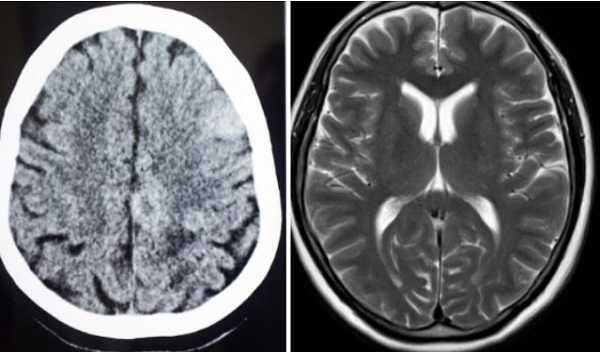

МР- и КТ- снимки поясничного отдела позвоночника

Особенности технологии играют ключевую роль при выборе метода диагностики. Главное отличие МРТ от МСКТ — физические явления, лежащие в основе обследований. Магнитный резонанс представляет собой временный обратимый процесс, абсолютно безвредный для организма. МРТ применяют для диагностики заболеваний у детей и беременных женщин (со второго триместра). Ограничений относительно кратности и частоты проведения исследования не существует. Процедура имеет противопоказания: МРТ недопустима для лиц с электронными и металлическими имплантатами.

При выполнении компьютерной томографии Х-лучи могут неблагоприятно влиять на организм. Воздействие радиации повышает риск изменения генетического материала в клетках, потенциально способно угнетать кроветворение, провоцировать развитие онкологических заболеваний. МСКТ противопоказана беременным. Из-за существенной ионизирующей нагрузки процедуру назначают с учетом нормы воздействия радиации за год (до 5 мЗв).

При выборе метода диагностики учитывают особенности проведения процедуры. Нативная МРТ одной анатомической области занимает около 15 минут. Все это время нужно сохранять неподвижность, что затруднительно при остром болевом синдроме, после травм. МСКТ длится несколько секунд.